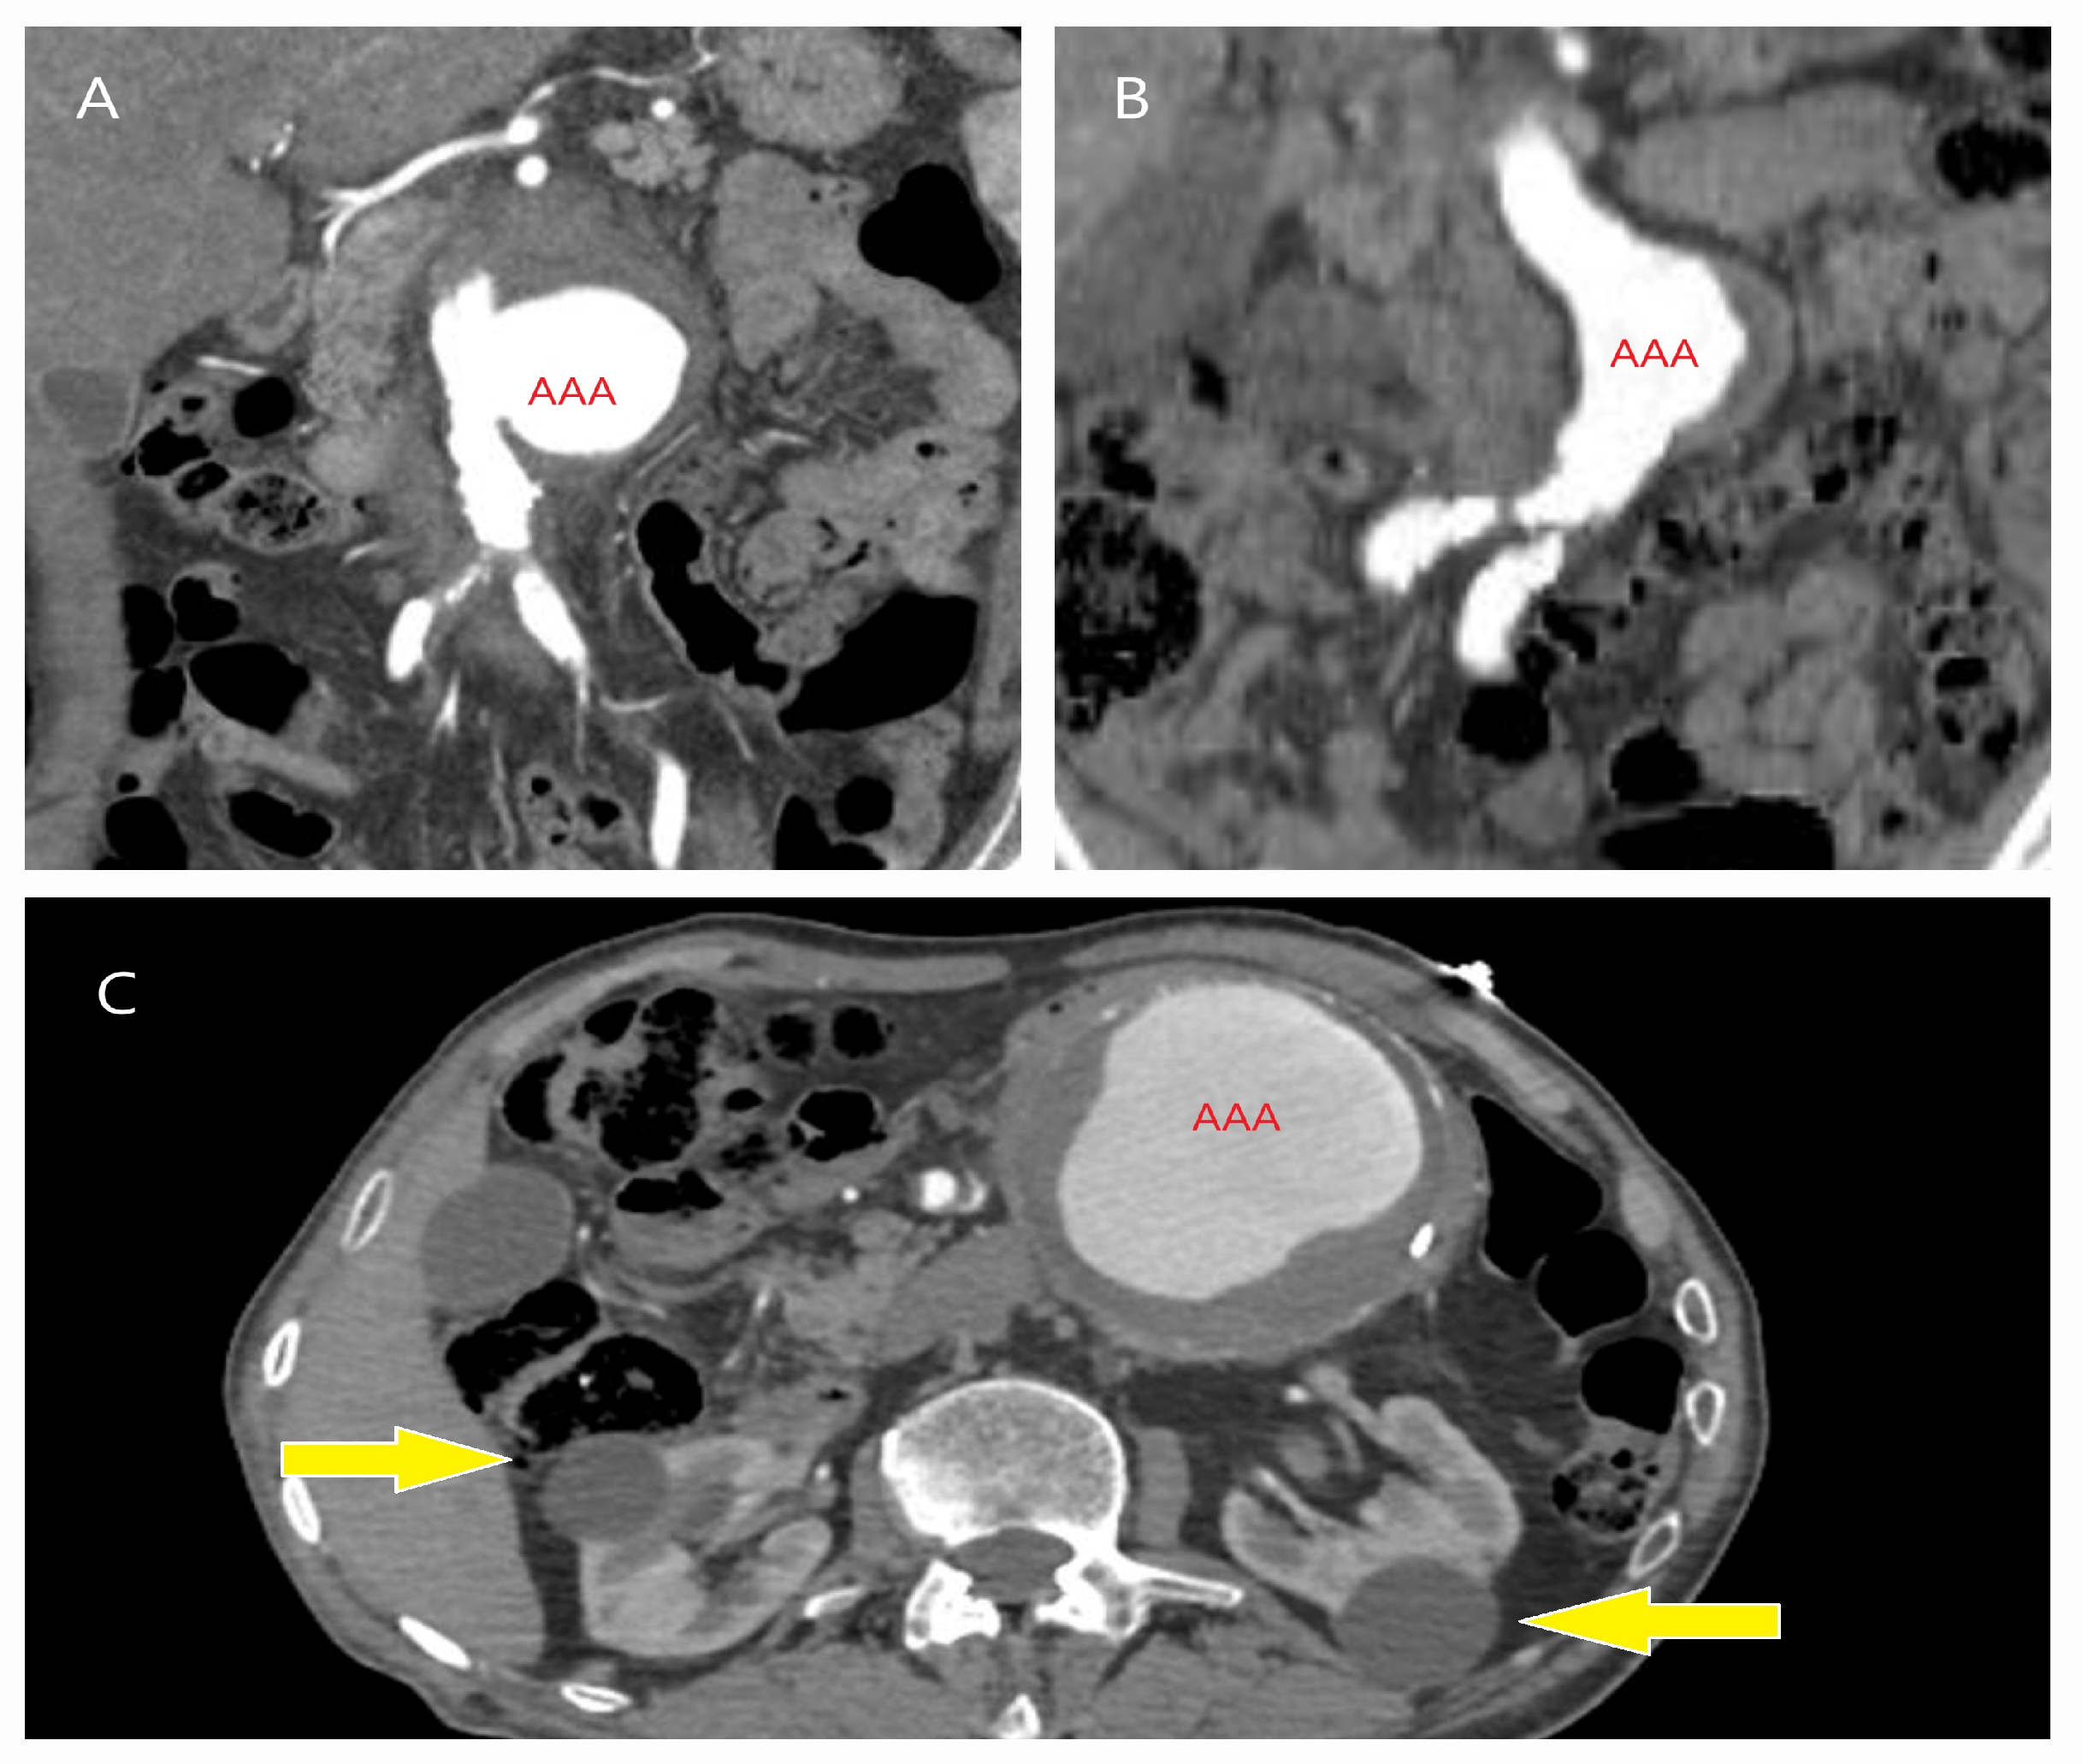

5.1. Failure of EVAR

5.2. Conversion to Open Surgery